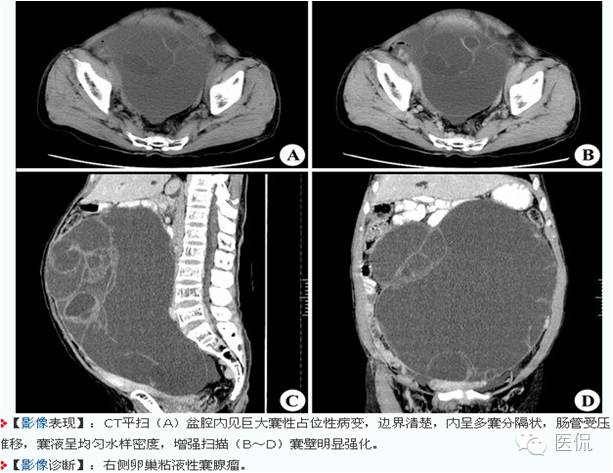

◆卵巢囊腺瘤

卵巢粘液性囊腺瘤